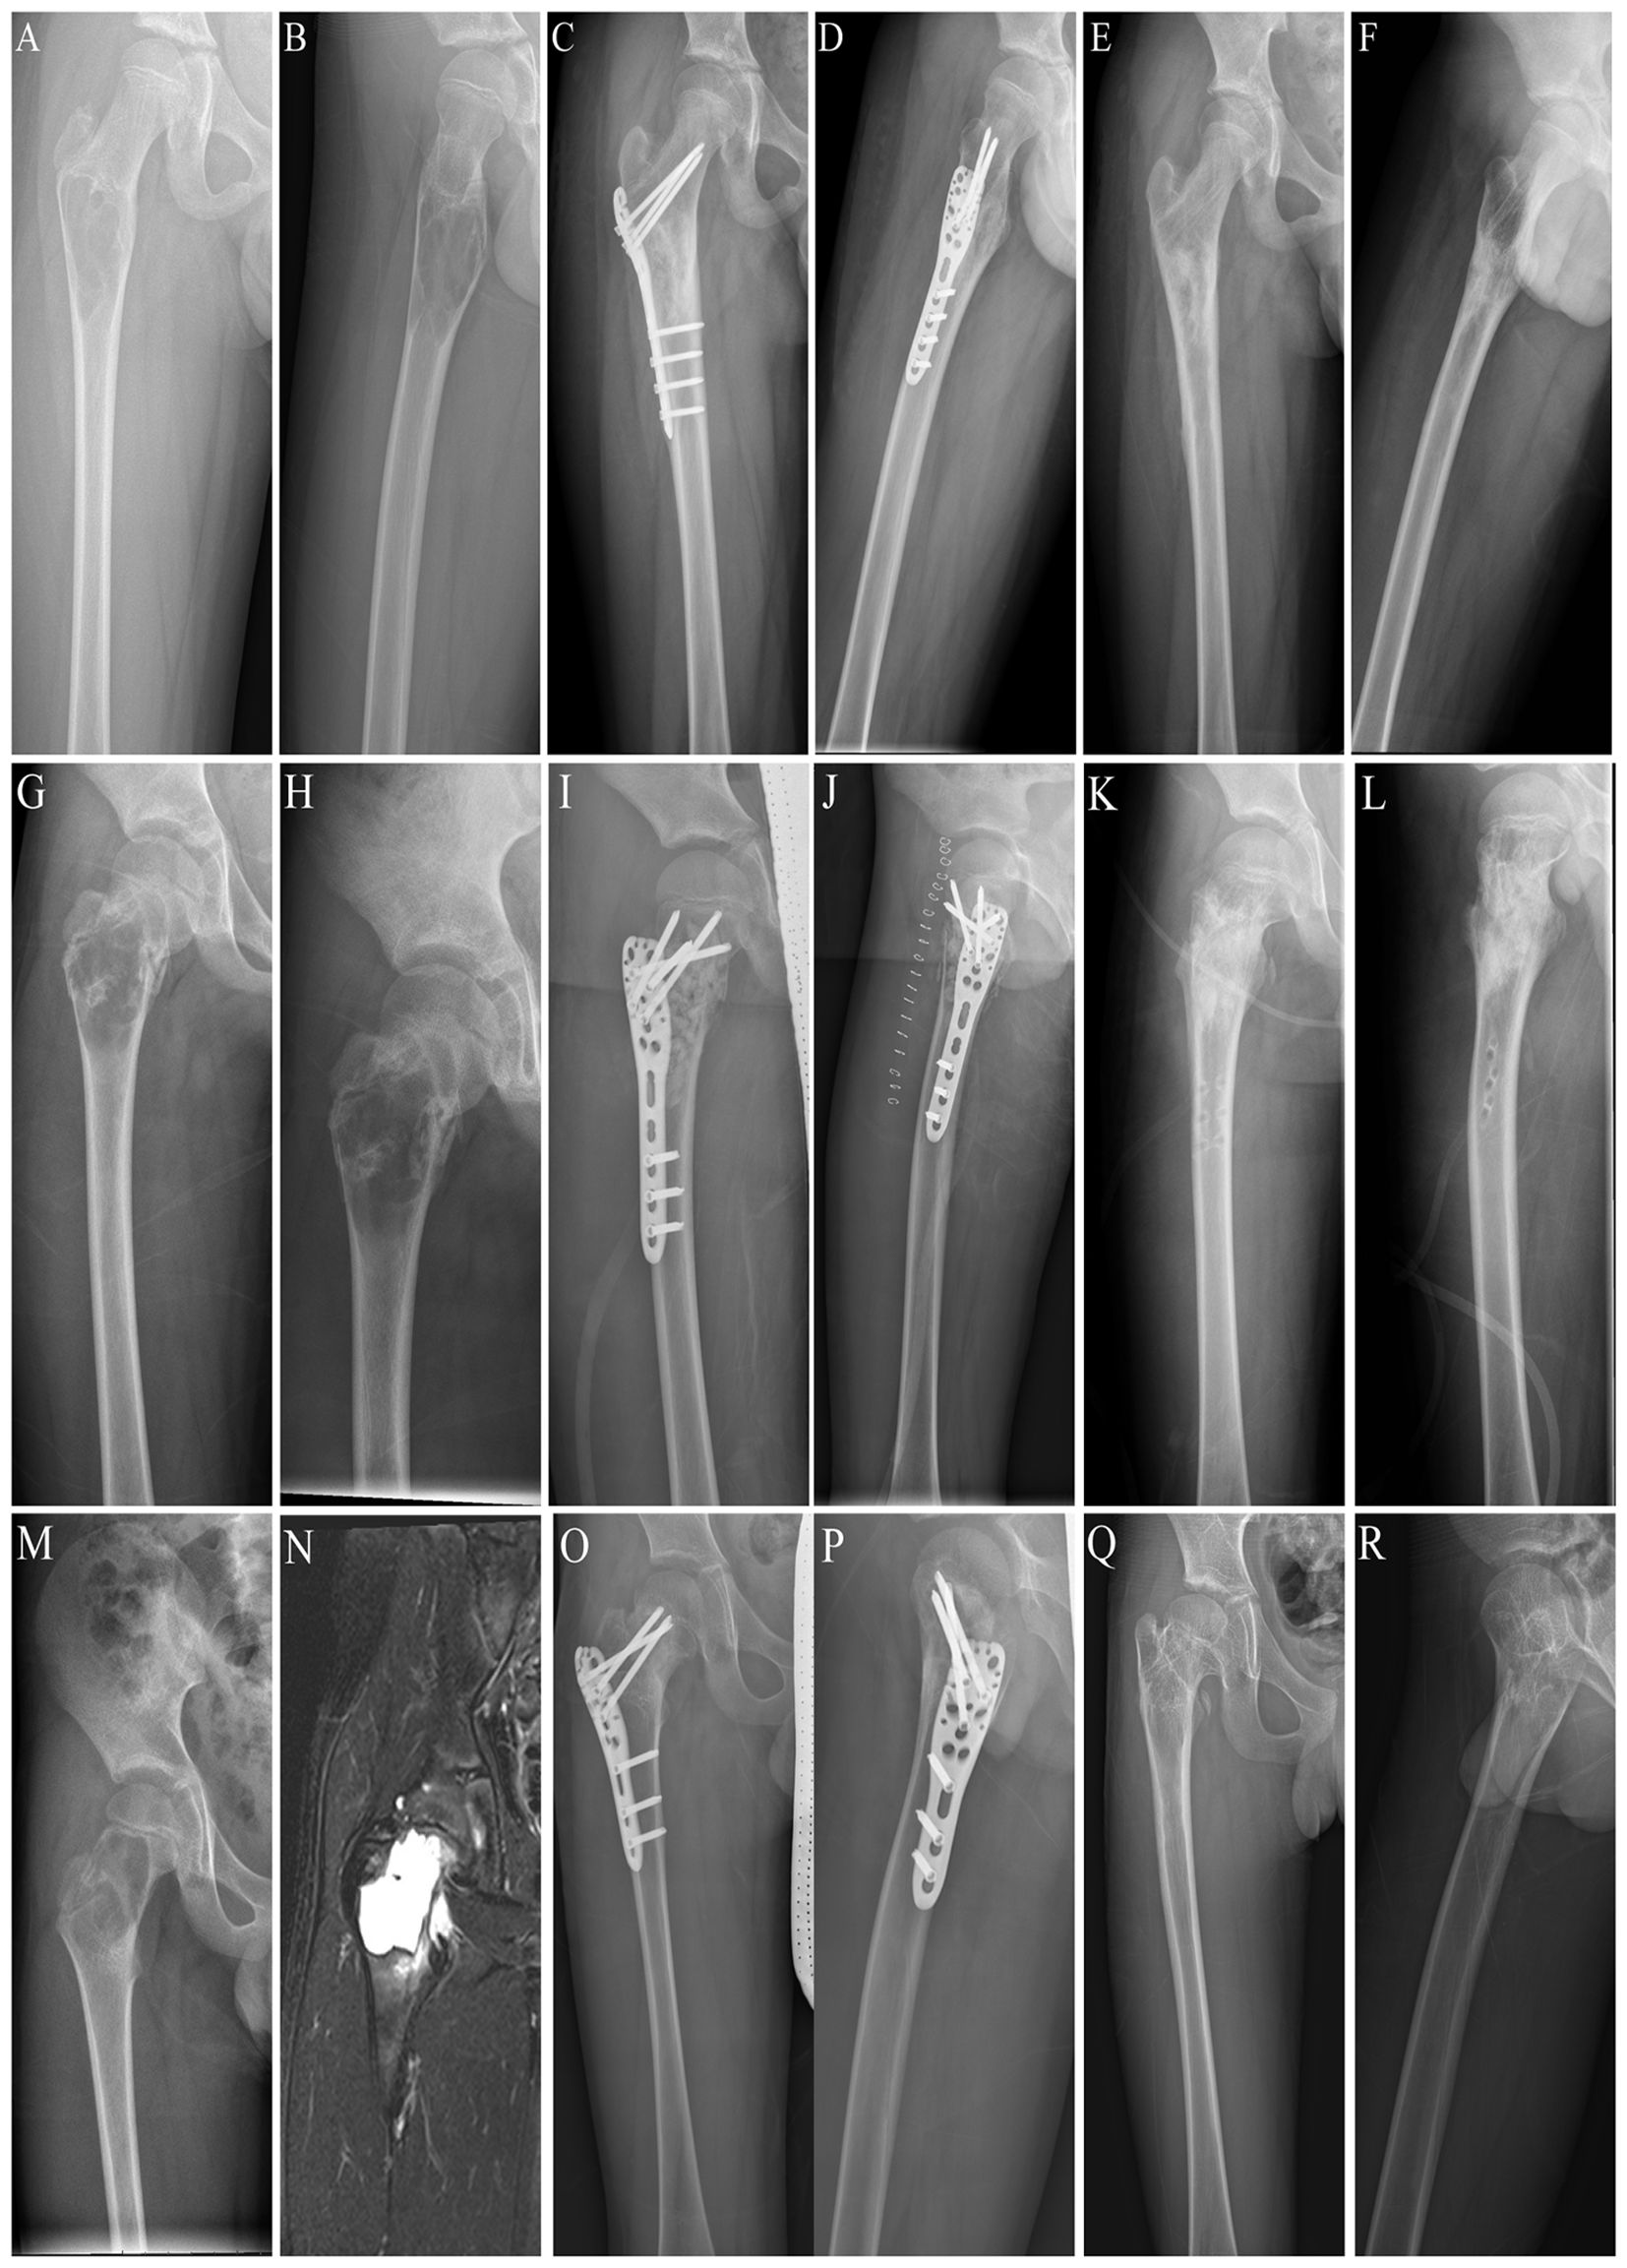

Patients with benign lesions of the proximal femur comprised three types of lesions, including BC (n = 2), ABC (n = 9), and FD (n = 11) (Table 1) (Figure 4). The postoperative pathology of all cases was consistent with the preoperative or intraoperative frozen biopsy findings, and none was misdiagnosed. Based on the affected part of the femur, patients were divided into three groups, including the subtrochanteric part (n = 13), intertrochanteric part (n = 5), and both intertrochanteric part and femoral neck (n = 4) (Figure 5). For each patient, a mean of 3 (95% CI, 2 to 4) locking screws were placed into the femoral neck to secure the locking plate at the proximal end of the femur. In contrast to conventional bone plates, no screws passed through the epiphysis or into the femoral head.

Figure 4. The three types of benign lesions were treated in this study. (A) Preoperative posteroanterior x-ray image of a patient with a pathological fracture of the left proximal femur caused by BC. (B) Preoperative lateral x-ray image of a patient with a pathological fracture of the left proximal femur caused by BC. (C) Postoperative posteroanterior x-ray image of a patient with BC of the left proximal femur. (D) Postoperative lateral x-ray image of a patient with BC of the left proximal femur. (E) Postoperative pathologic image of BC. (F) Preoperative posteroanterior x-ray image of a patient with a pathologic fracture of the left proximal femur caused by ABC. (G) Preoperative lateral x-ray image of a patient with a pathological fracture of the left proximal femur caused by ABC. (H) Postoperative posteroanterior X-ray image of one patient with ABC of the left proximal femur. (I) Postoperative lateral x-ray image of a patient with ABC of the left proximal femur. (J) Postoperative pathological image of ABC. (K) Preoperative posteroanterior x-ray image of one patient with a pathological fracture of the left proximal femur caused by FD. (L) Preoperative lateral x-ray image of a patient with a pathological fracture of the left proximal femur caused by FD. (M) Postoperative x-ray image of a patient with FD of the left proximal femur. (N) Postoperative lateral x-ray image of a patient with FD of the left proximal femur. (O) Postoperative pathologic image of FD.

Figure 5. Three different locations of benign lesions of the proximal femur. (A) Preoperative posteroanterior x-ray of a subtrochanteric lesion. (B) Preoperative lateral x-ray image of a subtrochanteric lesion. (C) Postoperative posteroanterior x-ray image of the internal fixation for a subtrochanteric lesion. (D) Postoperative lateral x-ray image of the internal fixation for a subtrochanteric lesion. (E) Posteroanterior x-ray image after removing the locking plate and screws from the subtrochanteric lesion. (F) Lateral x-ray image after removing the locking plate and screws from the subtrochanteric lesion. (G) Preoperative posteroanterior x-ray image of an intertrochanteric lesion. (H) Preoperative lateral x-ray image of an intertrochanteric lesion. (I) Postoperative posteroanterior x-ray image of internal fixation for an intertrochanteric lesion. (J) Postoperative lateral x-ray image of the internal fixation for an intertrochanteric lesion. (K) Posteroanterior x-ray image after removal of the locking plate and screws from the intertrochanteric lesion. (L) Lateral x-ray image after removing the locking plate and screws from the intertrochanteric lesion. (M) Preoperative posterior x-ray images of the intertrochanteric part and the femoral neck lesion. (N) Preoperative lateral x-ray image of the intertrochanteric segment and the femoral neck lesion. (O) Postoperative posteroanterior x-ray image of internal fixation for the intertrochanteric part and the femoral neck lesion. (P) Postoperative lateral x-ray image of internal fixation for the intertrochanteric part and the femoral neck lesion. (Q) Posteroanterior x-ray image of the intertrochanteric part and femoral neck lesion after removing the locking plate and screws. (R) Lateral x-ray image after removing the locking plate and screws from the intertrochanteric and femoral neck lesions.